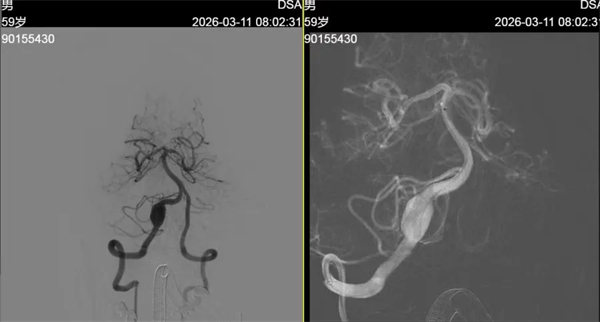

该患者平素身体健康,无基础疾病史,因发作性头晕症状入院检查。入院后,迅速为其完善头颅CT及MRI检查,初步发现双侧额顶叶及侧脑室体旁腔梗灶,且右侧椎动脉V4段存在瘤样扩张,高度怀疑颅内动脉瘤。为进一步明确病变细节,神经内一科团队及时为患者实施全脑血管造影术(DSA),最终确诊为右侧椎动脉V4段梭形动脉瘤,瘤体大小约13mm×20mm。

椎动脉V4段位于脑干核心区域,血管位置深、毗邻结构复杂,该部位动脉瘤破裂风险极高,堪称“生命禁区”里的高危隐患。针对患者动脉瘤的大小、形态及特殊位置,医院立即启动多学科会诊(MDT)机制,神经外科、影像科、麻醉科等多学科专家联合研判,综合评估手术风险与获益,一致认为椎动脉巨大动脉瘤病情凶险,外科手术开刀手术创伤大、风险高、技术要求高。密网支架治疗椎动脉动脉瘤手术微创、成功率高、并发症低,最终制定血流导向装置(密网支架)植入的个体化治疗方案。该技术可通过渐进式血流重建,引导血流正常流通,促使瘤体逐渐闭塞,最大程度保护脑干功能,降低手术风险。

在完善术前准备后,手术团队精准操作,顺利为患者植入血流导向装置。术后即刻造影显示,动脉瘤体内血流速度明显减慢,手术取得预期效果。术后,医护团队为患者制定个性化康复与用药方案,叮嘱患者规律服药,预计3-6个月后动脉瘤将完全闭塞,脑血管实现完美重建。目前患者恢复良好,头晕症状显著缓解,已顺利进入术后康复阶段。